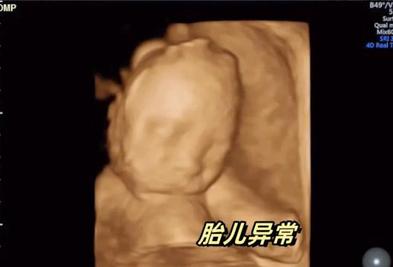

产检时发现胎宝没手没脚,孕妈却不顾大家的反对,产下娃,现状如何? 怀孕让每一位妈妈的心里都充满了对未来宝宝的无限憧憬——愿他健康聪明,愿他在阳光下自由奔跑,每一个角落都充满笑声。 但是,当这种期待受到现实的冷酷考验,当产前检查的结果像一把重锤,打破了孕妈妈和家人所有 2024-12-11